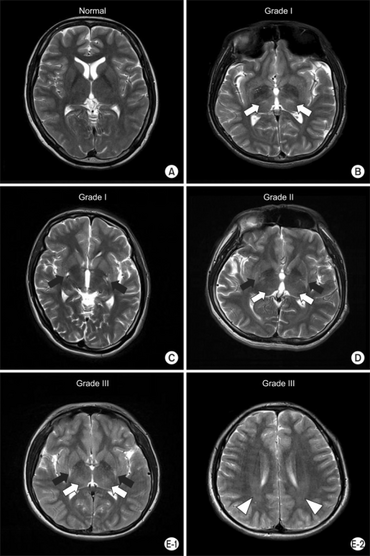

MRI image. a) Normal b) Grade 1- bilateral focal hyperintensity of thalamus -see arrows c) Grade 1- bilateral focal hyperintensity of putamen -see arrows d) Grade 2- bilateral focal hyperintensity of putamen -see black arrows and thalamus -see white arrows e1) Grade 3- bilateral focal hyperintensity of putamen -see black arrows and thalamus -see white arrows e2) Grade 3-bilateral diffuse hyperintensity of periventricular white matter -see arrow